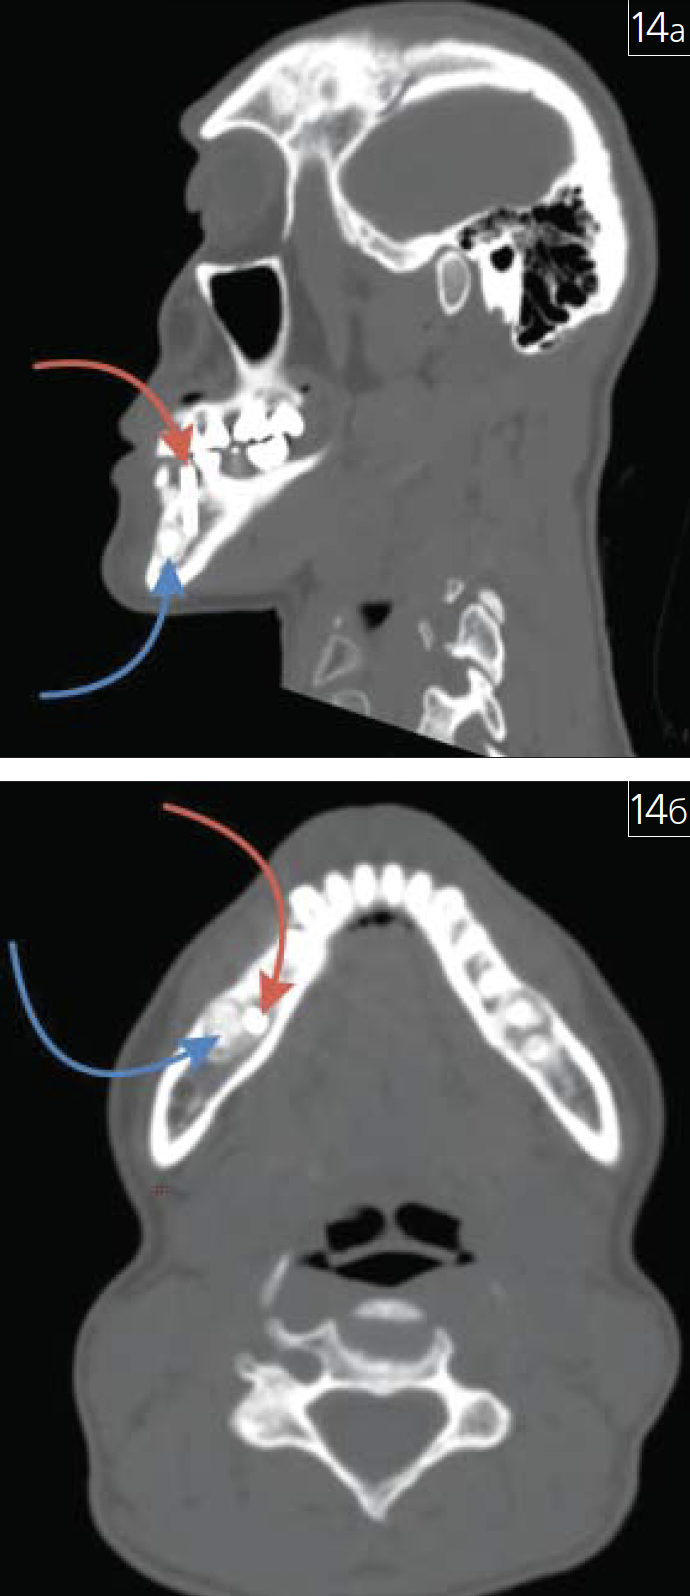

Особое место в практике врача-стоматолога, челюстно-лицевого хирурга и рентгенолога занимают ятрогении (рис. 13 а-в; 14 а, б; 15 а-в; 16; 17).

Рис. 14. Дентальный имплантат (указанкрасной стрелкой), установленный в областиодонтомы нижней челюсти (указана синейстрелкой): а – косая проекция МСКТ;б – аксиальная проекция МСКТ черепа